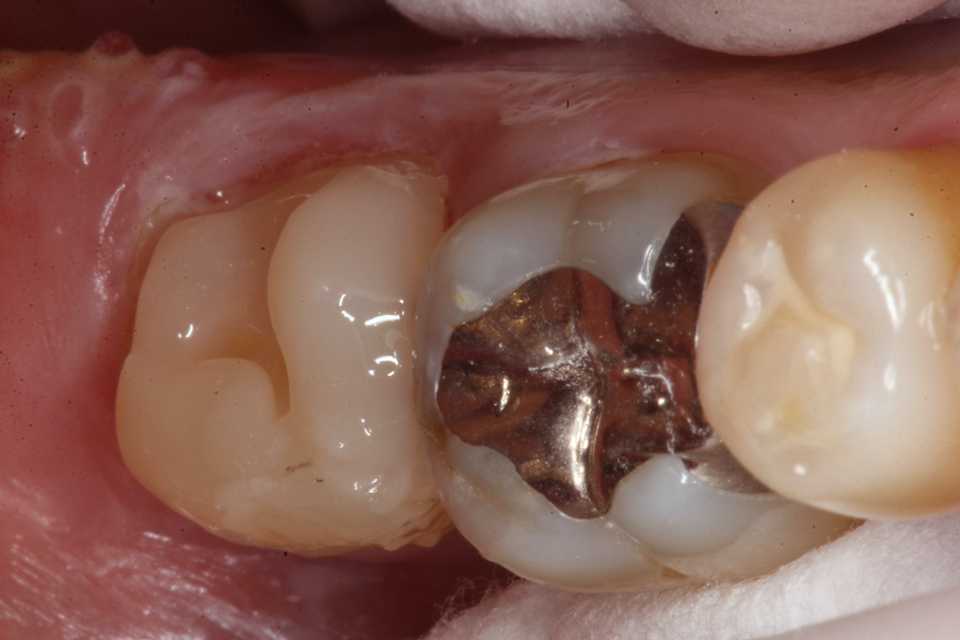

ストリップスを使わない隣接面CR(ダイレ… 2025.11.26

ストリップスを使わない隣接面CR(ダイレ… 2025.11.07